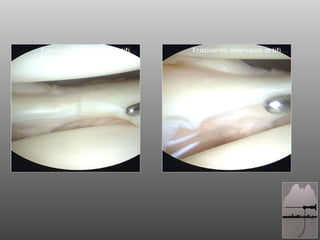

SCAFFOLD MENISCALE Impiantabile per via artroscopica  Biocompatibile  Bioriassorbibile  Forma fisica simile a quella del menisco umano  Adattabile alle dimensioni del difetto ACTI fit

SCAFFOLD MENISCALE ACTI fit Struttura porosa per facilitare la crescita cellulare al suo interno  80% Policaprolattone (polimero biodegradabile FDA-approved) 20% Uretano  (Degradazione lenta 4-6-aa macrofagi – cellule giganti)

SCAFFOLD MENISCALE Impiantabileper via artroscopica Biocompatibile Bioriassorbibile Forma fisica simile a quella del menisco umano Adattabile alle dimensioni del difetto ACTI fit

SCAFFOLD MENISCALE ACTIfit Struttura porosa per facilitare la crescita cellulare al suo interno 80% Policaprolattone (polimero biodegradabile FDA-approved) 20% Uretano (Degradazione lenta 4-6-aa macrofagi – cellule giganti)